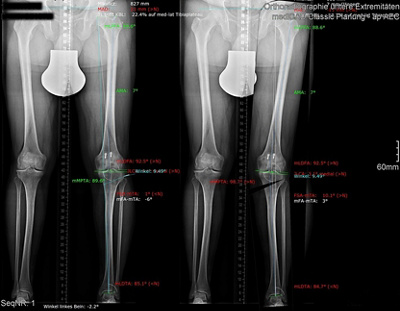

Dr. med. Alexander Strehl: Bei einer Umstellungsosteotomie wird die Lastachse im Knie und somit auch auf den Knorpel korrigiert. Korrekterweise geht die Belastung vom Oberschenkelkopfzentrum zum Sprunggelenkszentrum etwa mittig durchs Knie. Bei O- oder X-Beinen weicht diese Achse ab. Dies kann aus unterschiedlichen Gründen sein, zum Beispiel durch einen früheren Beinbruch oder weil der Patient in der Zeit des Skelettwachstums viel Fussball gespielt hat, kommt aber auch oft ohne eigentliche Ursache vor. Das O-Bein ist häufiger als das X-Bein. Manchmal sieht man diese Abweichung der Beinachse nicht auf den ersten Blick, sondern erst mit einer Ganzbeinstandaufnahme.

Durch O- oder X-Beine wird der Knorpel im Knie einseitig belastet. Da reichen manchmal schon wenige Millimeter, die die Achse abweicht. Folge ist, dass sich eine Knorpelseite deutlich schneller abnutzt als die andere. Mit der Operation wird die Belastung zurück auf die Mitte gesetzt oder eine kleine Überkorrektur auf die gesunde Seite vollzogen, sodass diese etwas mehr belastet und die abgenutztere Seite entlastet wird.

Dr. med. Alexander Strehl: Bei der häufigsten Umstellungsosteotomie am Unterschenkelkopf macht man einen Sägeschnitt am Knochen, klappt diesen gezielt auf und fixiert ihn mit einer winkelstabilen Platte; dies auf Basis dessen, was man vor der Operation bei der Planung gemessen und errechnet hat. Es entsteht ein winkelförmiger Spalt im Knochen, der von selber wieder zuwächst. Je nach Ort und Art der Deformität findet auch der Eingriff statt. Bei einem O-Bein ist dies meistens am Unterschenkelkopf. Es können aber auch Eingriffe am Oberschenkel nötig sein, vor allem beim X-Bein. Bei extremen Deformitäten kann auch eine Doppelosteotomie erforderlich sein, also dass man am Ober- und Unterschenkel korrigieren muss, um wieder eine gerade Achse zu erhalten. Dies muss man im Vorfeld genau analysieren und planen. Während der Operation wird die Beinachse mehrfach mit dem Ausrichtestab überprüft.